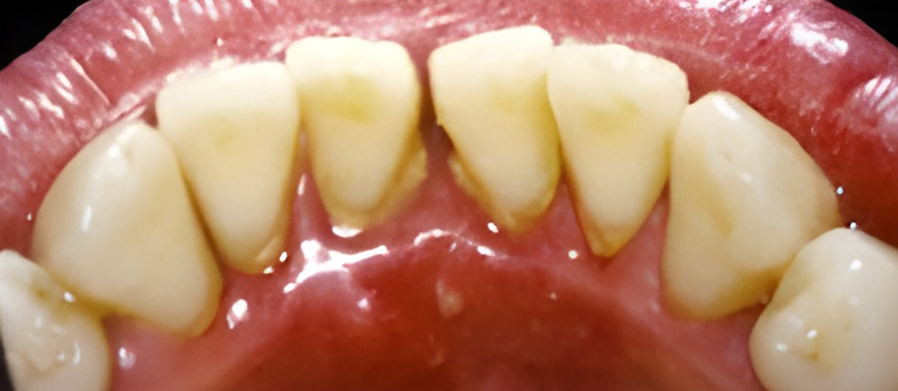

치주염은 스케일링을 통해 플라그와 치석을 제거하여 치료합니다. 문제가 되는 치주낭 부분을 제거하여 건강한 조직이 치아에 붙을 수 있도록 합니다.

잇몸이 심하게 붓고 피가 자주 나며 치가가 흔들리기도 합니다. 치아 뿌리가 드러나기도 하며 때로는 잇몸에 고름이 나와 음식물을 잘 씹을 수가 없습니다.

잇몸에 고름이 차 있다면 배농이 필요하고, 잇몸을 절개해서 염증조직을 제거하거나 치은이나 뼈를 이식하는 수술을 시행하기도 합니다.